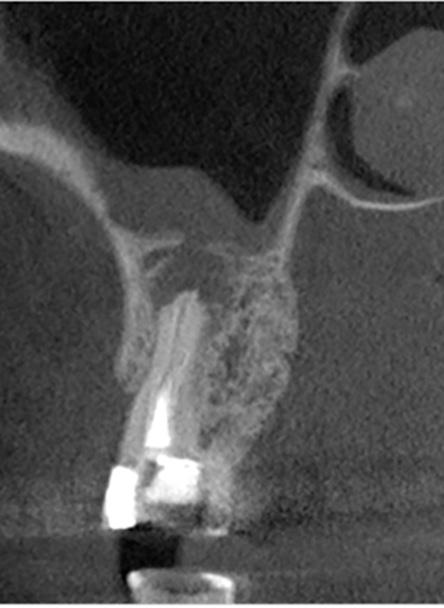

| A Tomografía computarizada de haz cónico (CBCT) coronal o sagital que muestra la proximidad de la lesión periapical y el seno maxilar. | B Oclusión correcta antes del tratamiento. | C Plantilla quirúrgica 3D para guiar el acceso. | D Osteotomía con el Piezotome Cube (Acteon, EE. UU.) usando la punta SL1 después de elevar el colgajo. | D Osteotomía con el Piezotome Cube (Acteon, EE. UU.) usando la punta SL2 | F Preparación retrógrada sobre la raíz mesiovestibular con una punta Berutti (EMS, Suiza) e irrigación salina. | G Biocemento Bio C Repair (Angelus, Brasil) aplicado en el conducto mesiovestibular. | H Fotografía con el microespejo de 3 mm para comprobar la obturación retrógrada en la raíz distovestibular del segundo molar derecho superior. | I Geistlich Bio-Oss® Small 0,5 g. (Geistlich Pharma AG, Suiza) en el sitio quirúrgico. | J Cavidad quirúrgica rellenada con Geistlich Bio-Oss® Small. | K Membrana Geistlich Bio-Gide® 25 × 25 mm usada para cubrir el injerto. | L Radiografía final después de la cirugía.

FIG. 1: Microcirugía periapical regenerativa para tratar la periodontitis apical alrededor de las raíces mesiovestibular y distovestibular del diente

La microcirugía periapical regenerativa incluye los siguientes pasos (figura 1):

1. Aumento mejorado para una resección mínima de la raíz;

2. Preparación ultrasónica del ápice de la raíz;

3. Obturación retrógrada con un mate rial biocerámico para la reparación de la raíz; y

4. Regeneración tisular guiada en el lu gar del defecto óseo.

Los índices del éxito de la microcirugía periapical regenerativa han aumentado de manera notable en los últimos años gracias a los avances en las técnicas di gitales para la planificación, la microsco pía, los instrumentos microquirúrgicos y los biomateriales para la regeneración ti sular guiada.3 4

Uso biomateriales para las microcirugías periapicales y, hasta la fecha, estoy muy satisfecho con los resultados clínicos. El protocolo me ha permitido ayudar a mu chos pacientes a conservar sus dientes naturales insalvables, y a mantenerlos sanos y funcionales. Recientemente, mis colegas y yo publicamos un caso clínico donde detallábamos el protocolo y el re sultado clínico en el manejo de una lesión radicular grande mediante microcirugía periapical regenerativa.3 El quiste medía 40 mm en la zona más grande, y afectaba a varios dientes anteriores, a ambas placas corticales y en parte al suelo nasal. Debi do a las grandes dimensiones del defecto, decidimos usar una mezcla de Geistlich Bio‑Oss® y hueso autógeno obtenido de la rama ascendente de la mandíbula, junto con fibrina rica en plaquetas. El resulta do clínico era satisfactorio 4 años después de la cirugía (es decir, en el momento de la publicación). Además, cuando estudia mos las imágenes de la tomografía com putarizada de haz cónico, observamos que los tejidos estaban bien integrados, había hueso cortical nuevo y una radio pacidad y una forma trabecular parecidas a las del hueso nativo adyacente.